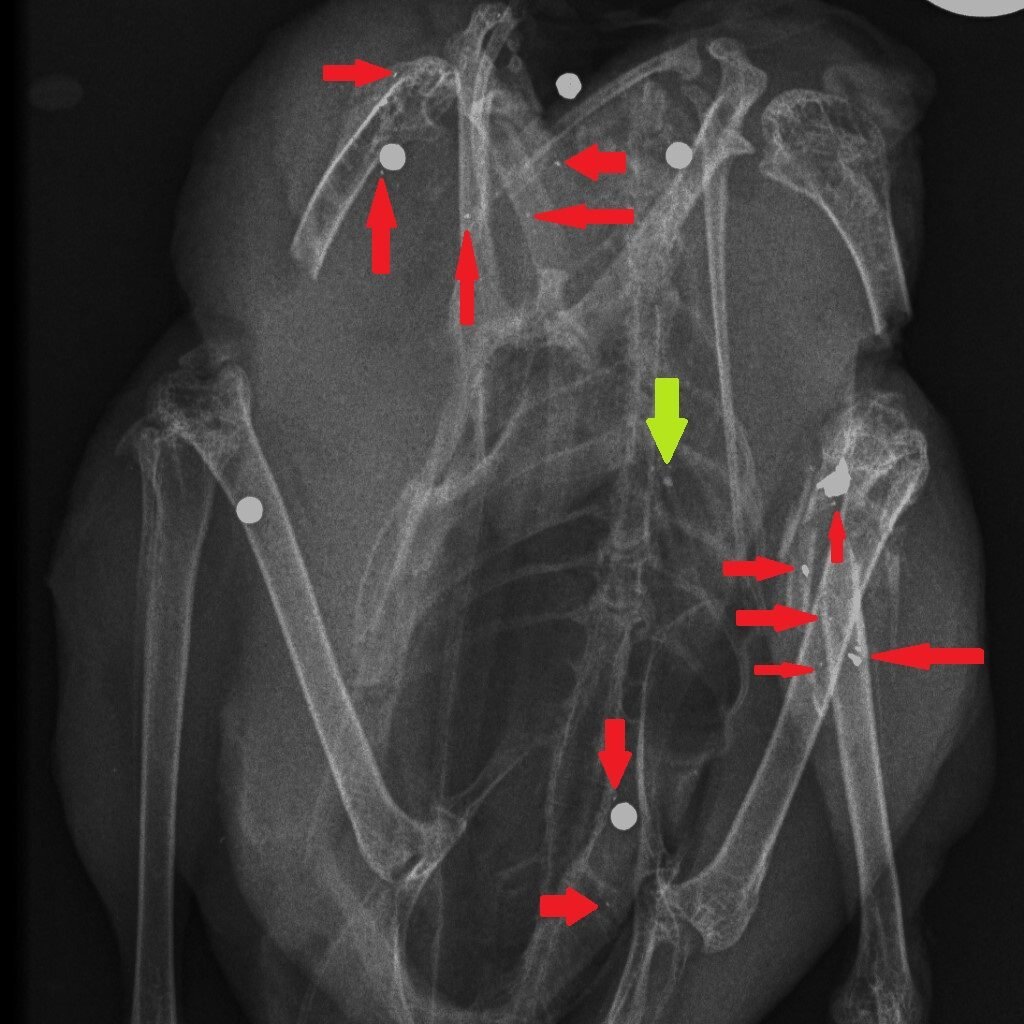

How could we reduce the risk of exposure to lead in game meat? It’s simple – stop shooting lead ammunition into animals that are destined for the human food chain. One of the useful properties of lead is that it is soft and malleable – that’s why, in the past, we have used it widely. But those same physical properties mean that lead passing through the flesh of a shot animal, hitting organs, soft tissue, bones and cartilage, shatters and tiny fragments of lead spread through the body of the animal. Here are three x-rays of shot birds that were bought in butcher’s shops and then x-rayed. The top x-ray is of a partridge and the other two are Red Grouse. Large white circular objects are lead shot. The green arrows point to fragments of bone and the red arrows indicate fragments of lead, from the shot, that have spread through the flesh.

Almost all of the fragments of lead are tiny – far too small to be detected in the cooking or eating process. Yes, you can spit out the almost-intact lead shot but you can’t get rid of the fragments. The lead analyses that have been done in studies cited above, and in our own, remove the lead shot and analyse the lead content of the meat after that removal. So when Sainsbury’s say that their game meat has no lead shot in it that’s good (although careful eating would remove those anyway) but they are not removing the tiny fragments of lead. So removing the almost intact lead shot particles is pretty irrelevant to the lead levels in the meat, as we will show you later this week…